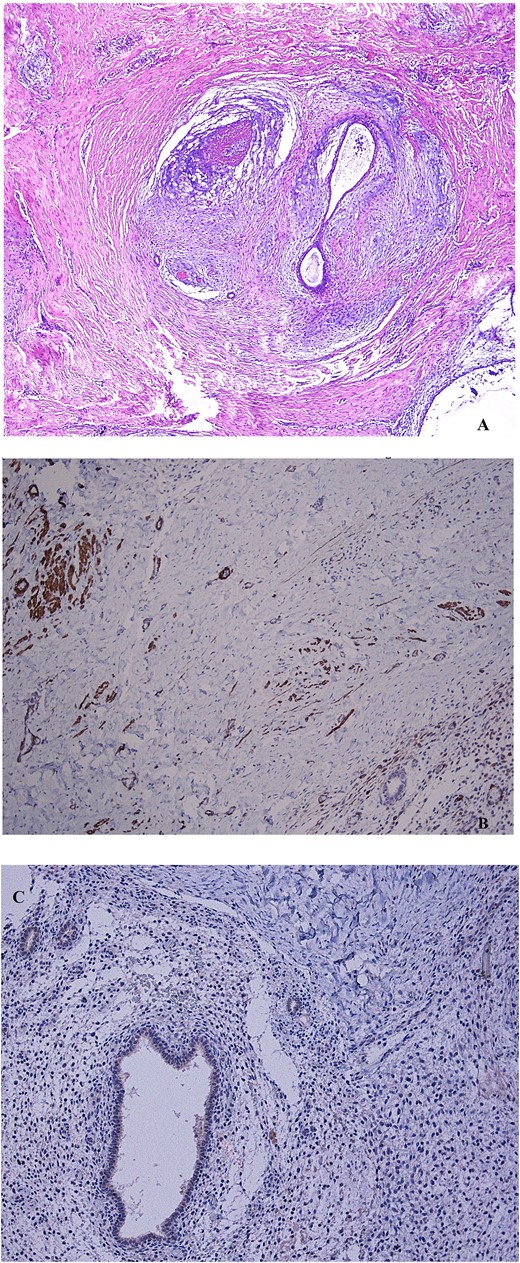

(A) Non atypical endometrial glands and stroma, surrounded by smooth muscle tissue, representing the mainstay features of adenomyoma, are shown after hematoxylin–eosin stain (4× magnification). (B) The immunohistochemical staining to desmin indicates the muscle cells counterpart of the mass (10× magnification). (C) The negative immunohistochemical staining to myogenin indicates a non-skeletal origin of muscle cells (10× magnification).